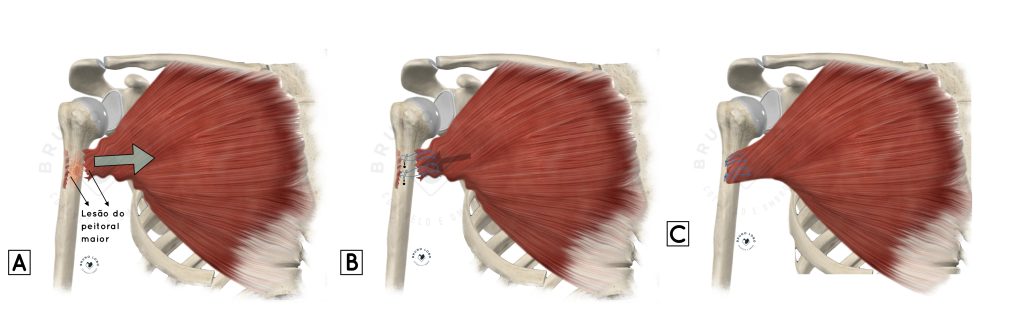

REPARO DO PEITORAL MAIOR – TÉCNICA CIRÚRGICA

O reparo do tendão do peitoral maior é realizado com um acesso no local de junção entre o braço e o peito. O tendão é localizado, desbridado e reinserido novamente no úmero. Essa fixação óssea do tendão pode ser feita de várias formas, incluindo diferentes dispositivos de fixação, como âncoras ou botões metálicos, ou com túneis ósseos.

Quando o tendão rompe completamente e o paciente demora a realizar a cirurgia, ocorre grande retração e aderências do tendão. Nestes casos, dependendo do tempo transcorrido, pode não ser possível recuperar toda a excursão do tendão. Dessa forma, pode ser necessária a utilização de um enxerto de tendão para reforçar e ganhar maior alcance do tendão para o reparo.